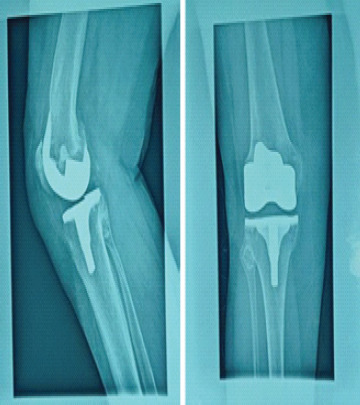

Case report: A 71-year-old Caucasian woman presented to our orthopedic department due to chronic right knee pain, which had worsened over the past year. She was diagnosed with osteoarthritis and was scheduled for a TKA. Three years postoperatively, she returned for examination due to anterior knee pain. Patellar instability was observed and intensive extensor mechanism strengthening and physiotherapy were recommended. Three months later, she presented with severe pain and inability to move her knee. Imaging revealed a fracture and dislocation of the patella. She was surgically treated with lateral release and proximal realignment of the extensor mechanism, according to Insall procedure, with great post-operative outcome.